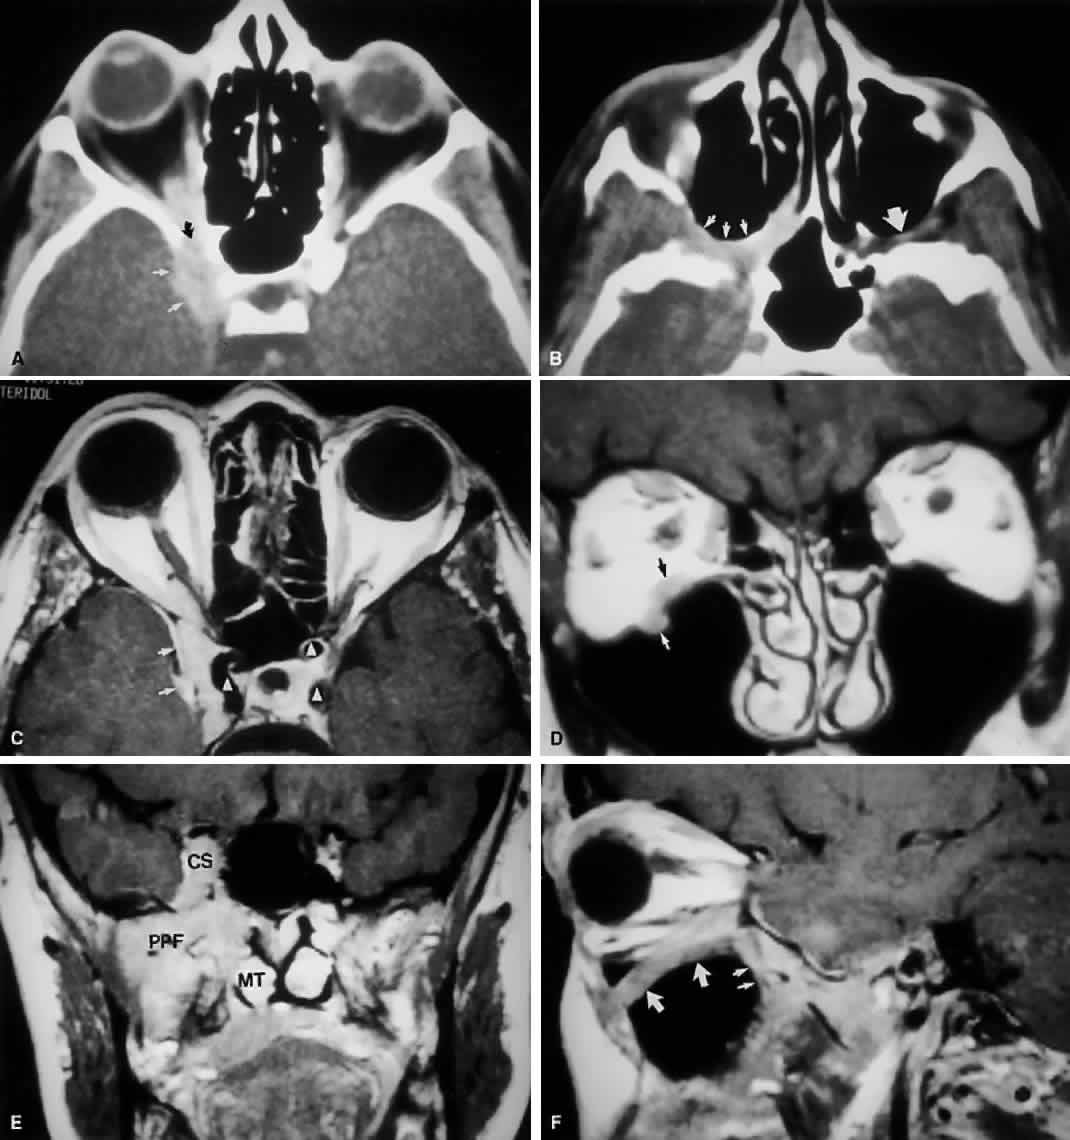

Radiographically, the spaces and foramina of the orbital apex may be considered to lie in three tiers (Fig. 8). The CS is found on the same level as the orbital apex, connecting directly with it via the superior orbital fissure (SOF) to form the middle tier. The inferior tier is formed by the inferior orbital fissure (IOF), which provides direct communication between the orbital apex and the pterygopalatine fossa, a vertically oriented space directly behind the maxillary sinus. Finally, the optic canal has no direct communication with any of the aforementioned spaces and should be considered to lie above the SOF and CS, exiting the orbit in a superomedial course through the body of the sphenoid as the superior tier.26 Orbital apical lesions can therefore gain ready access to the CS and pterygopalatine fossa (Fig. 9). Spread into the cranial vault through the optic canal is usually limited to lesions of the optic nerve (glioma) or nerve sheath (meningioma).

Fig. 9. An orbital lymphoma involving the skull base provides accentuation of the apical spaces of the orbit. A. On this axial CT, the lesion infiltrates the CS, causing bulging and local invasion of its lateral dural wall (small arrows). Invasion into the orbital apex through the superior orbital fissure (curved arrow) is seen. Note that the patient is slightly rotated in the scanner, because the anterior clinoid and optic canal are visualized on the uninvolved side. B. More inferiorly, the mass has invaded the pterygopalatine fossa (small arrows), located just posterior to the maxillary sinus. On the uninvolved side (large arrow), the fossa has areas of radiolucency, indicating the fat that normally occupies this space. C. Axial MRI, T1-weighted image with gadolinium but without fat suppression. The carotid siphon is seen within each CS as a flow void (arrowheads). Once again, note the inflamed lateral dural wall of the CS and local invasion of the brain parenchyma (small arrows).D. Coronal T1-weighted MR image. The inferior rectus muscle is labeled with a black arrow. The lymphoma has infiltrated the infraorbital canal (white arrow) within the orbital floor. E. Coronal MRI of the orbital apex shows infiltration from the CS to the pterygopalatine fossa (PPF). Because there is no direct communication between these spaces, the lesion must have spread through the superior orbital fissure into the orbital apex, then through the inferior orbital fissure. MT, middle turbinate. The lucency just above the CS is the anterior clinoid process, with the optic nerve within its canal seen as an opacity between the clinoid and the sphenoid sinus. F. Parasagittal MRI shows lymphomatous invasion of the pterygopalatine fossa just behind the posterior wall of the maxillary sinus (small arrows). Note the thickening of the infiltrated infraorbital canal (large arrows) as it travels anteriorly to exit about 1 cm below the inferior orbital rim.